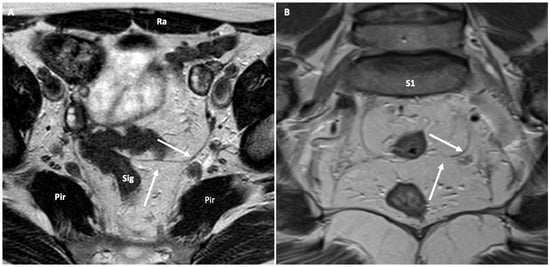

- Cul-de-Sac herniation: defined as an abnormal deepening of the pelvic peritoneum beyond the normal confines of the rectovaginal space or widening of the rectovaginal space containing fat, small bowel, or sigmoid colon.

- Rectocele: defined as an anterior protrusion of the rectal wall during evacuation, greater than 2 cm beyond the expected margin of a line extending upward from the anterior margin of the anal canal.

- Intussusception: defined as a full-thickness circumferential rectal wall invagination greater than 3 mm in thickness, descending toward the anal canal during evacuation but not extending beyond the anal verge. It is seen as a funnel-shaped infolding of the upper rectal wall, creating a “tube within a tube”. The thickness of the intraluminal defect, the depth of descent, and the distance from the point of inversion to the anal verge are measured.